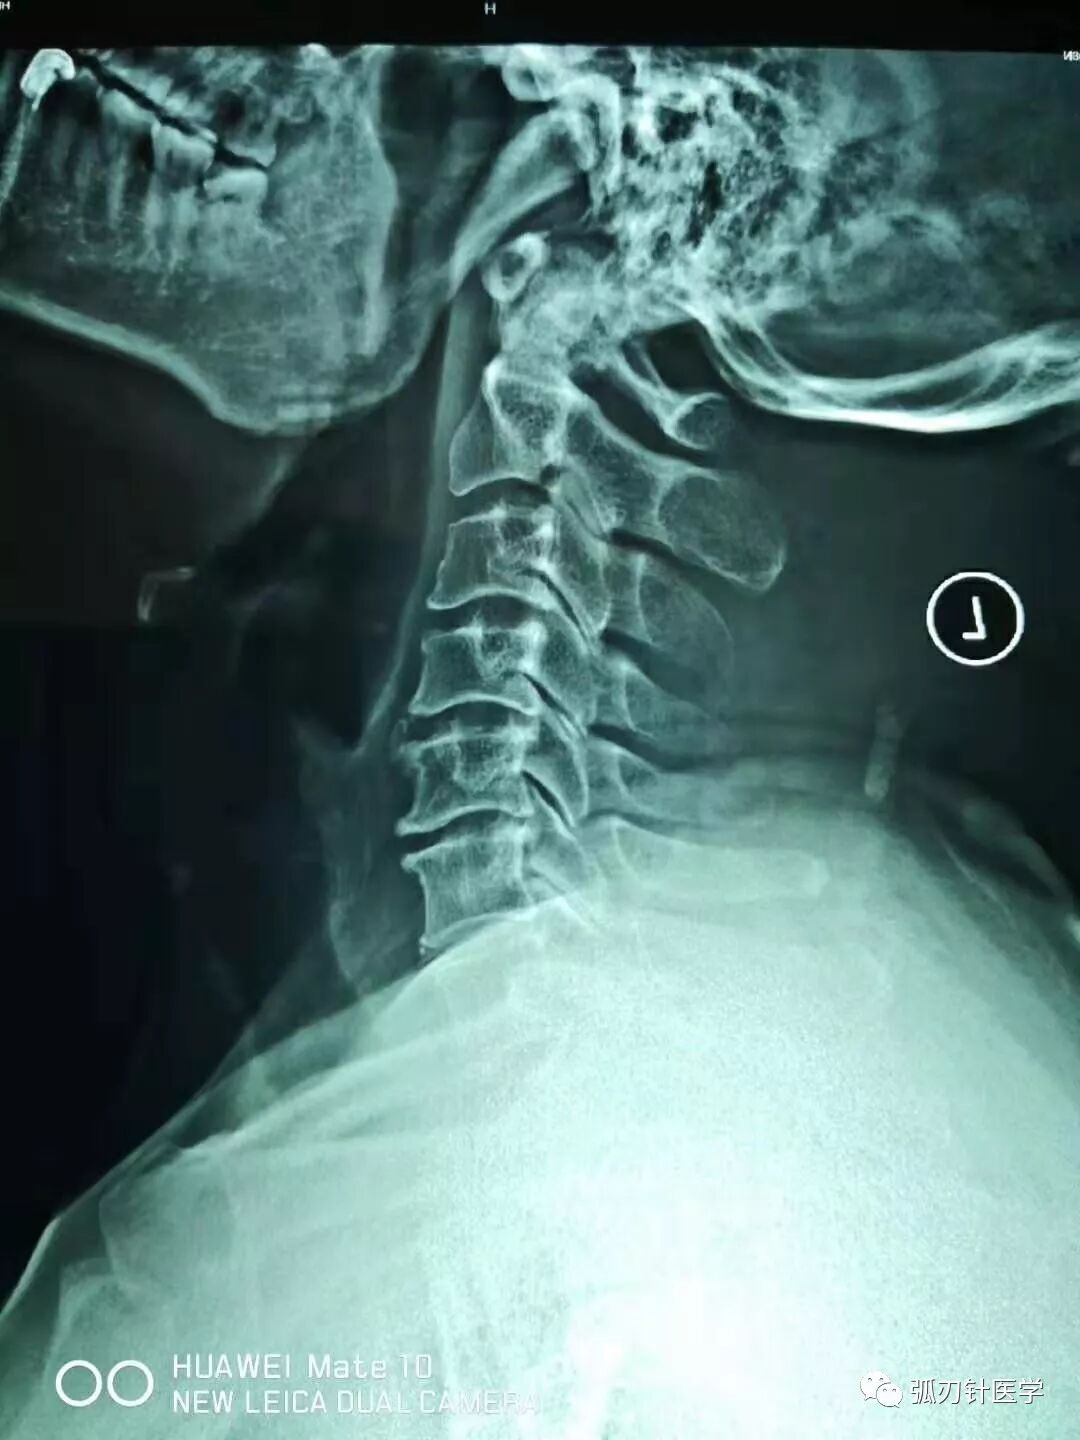

胳膊麻、脖子疼,一个中年男性患者典型的颈椎片和磁共振:骨质增生、项韧带钙化、椎间盘突出、椎间孔狭窄……